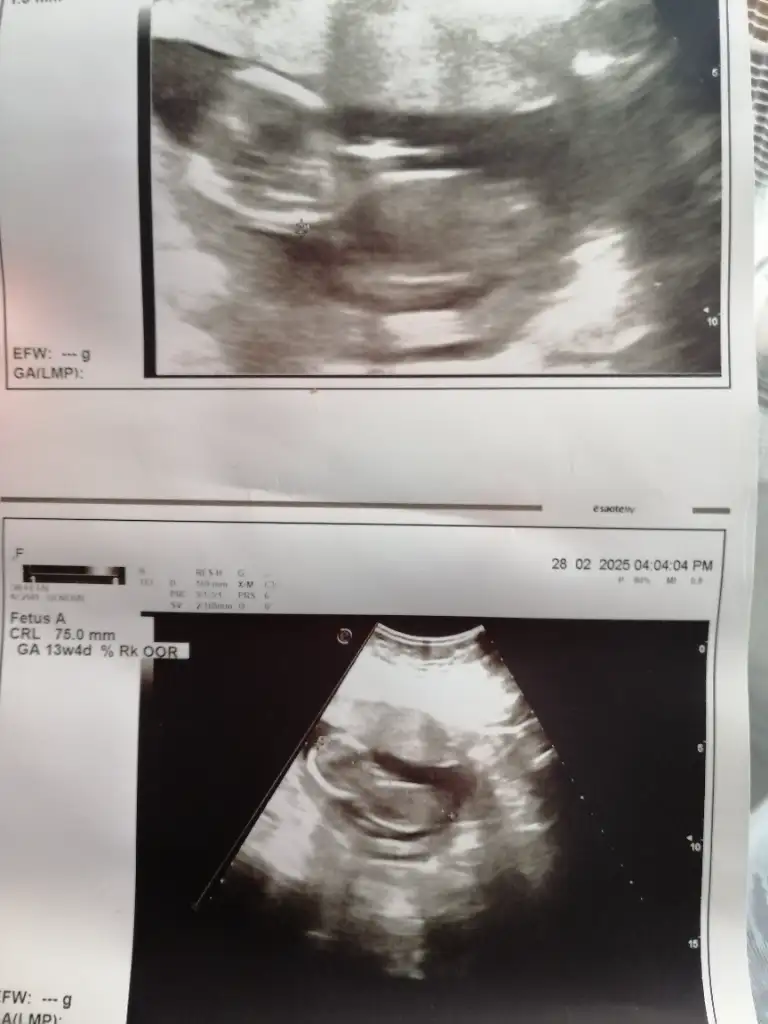

Z zeyyy123 Aktif Üye Kayıtlı Üye 4 Kasım 2024 1.111 489 43 29 28 Şubat 2025 Konu Sahibi Konu Sahibi xnadia99 #67 berrawst .!.: Kız bence Genişletmek için tıkla... Tahminde bulunabilirmisniz Eklentiler 1C089BDC-DF8E-48AF-B195-7FAE44235CB7.webp 46,2 KB · Görüntüleme: 31